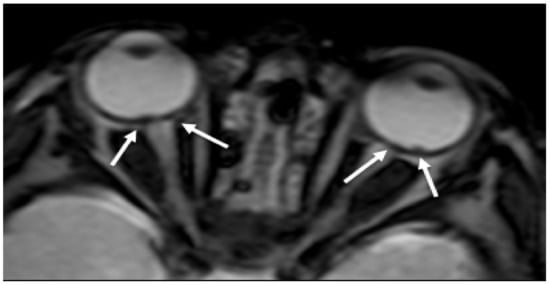

- Kemp, A.; Cowley, L.; Maguire, S. Spinal injuries in abusive head trauma: Patterns and recommendations. Pediatr. Radiol. 2014, 44, 604–612. [Google Scholar] [CrossRef] [PubMed]

- Koumellis, P.; McConachie, N.S.; Jaspan, T. Spinal subdural haematomas in children with non- Accidental head injury. Arch. Dis. Child. 2009, 94, 216–219. [Google Scholar] [CrossRef] [PubMed]

- Choudhary, A.K.; Bradford, R.K.; Dias, M.S.; Moore, G.J.; Boal, D.K.B. Spinal subdural hemorrhage in abusive head trauma: A retrospective study. Radiology 2012, 262, 216–223. [Google Scholar] [CrossRef] [PubMed]

- Choudhary, A.K.; Ishak, R.; Zacharia, T.T.; Dias, M.S. Imaging of spinal injury in abusive head trauma: A retrospective study. Pediatr. Radiol. 2014, 44, 1130–1140. [Google Scholar] [CrossRef] [PubMed]